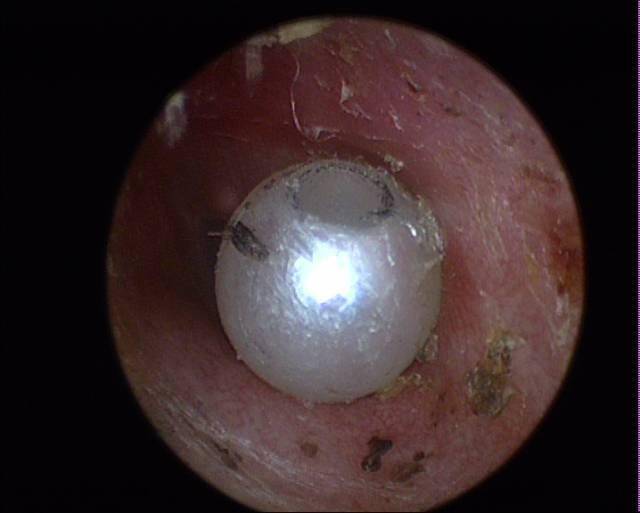

医生从她耳朵里找到白色的……_异物_麻醉_小蕊

图片尺寸1080x720